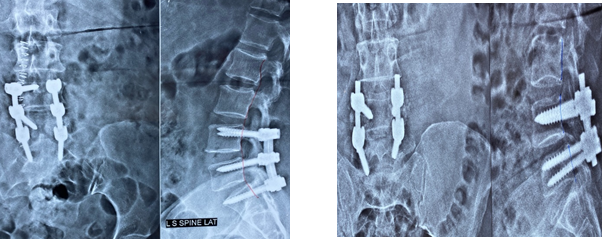

- Spinal fusion with bone graft either interbody or posterolateral is a standard surgical procedure.